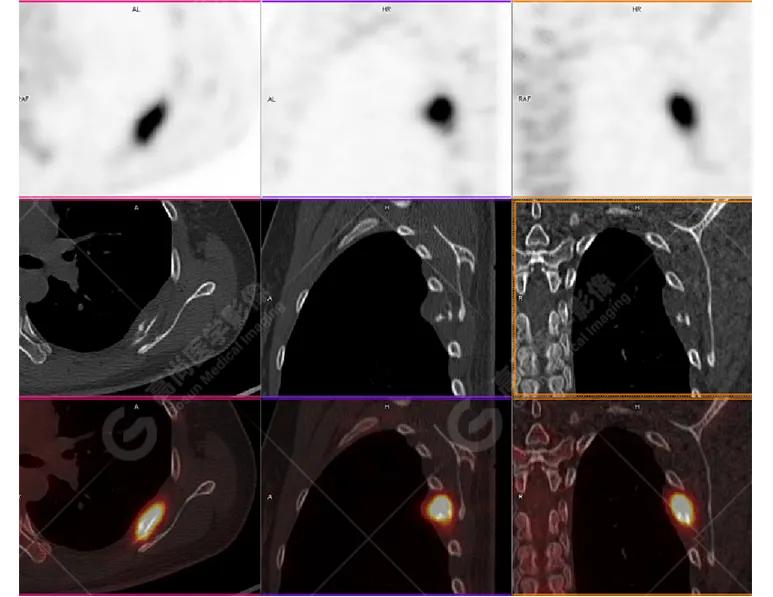

影像图

胸椎溶骨性骨质破坏,FDG环状代谢增高,SUVmax为4.0。

左侧乳腺一软组织结节,FDG代谢增高,SUVmax为2.6。

最终诊断: 左侧乳腺癌伴胸椎单发骨转移。